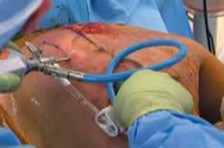

Portal Placement and Initial Access

- Landmarks: Key landmarks are palpated and marked on the skin: medial border of the scapula, superior and inferior angles, vertebral spinous processes. The area of maximal tenderness or palpable crepitus is also marked.

Working Space Creation:

Inferior Portal (Working/Viewing):

This is often the primary viewing portal. A 1-2 cm incision is made approximately 1-2 cm lateral to the medial border of the scapula, at the level of the inferior angle. This targets the infraserratus space.

- Through this incision, a blunt trocar is directed towards the scapulothoracic interval. Crucially, the trocar should be advanced parallel to the thoracic wall, hugging the undersurface of the scapula, to avoid lung injury. The serratus anterior muscle fibers will be encountered. The goal is to enter the infraserratus bursa, located between the serratus anterior and the chest wall.

Image:

Visualization of portal placement is key.

A clear entry point is vital.